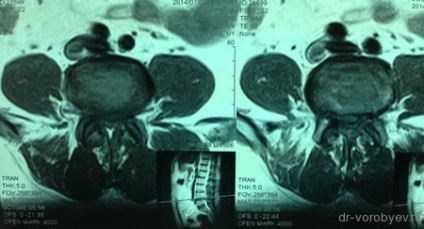

MRI az ágyéki gerinc műtét előtt, axiális vetülete.

MRI, sagittalis vetítés.